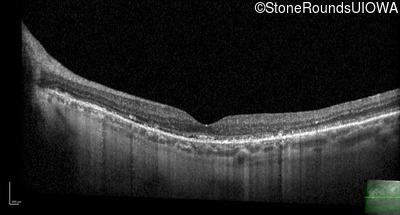

Optical Coherence Tomography - Left - 20/25 +3

Exemplar / OCT Stack

OCT Stack